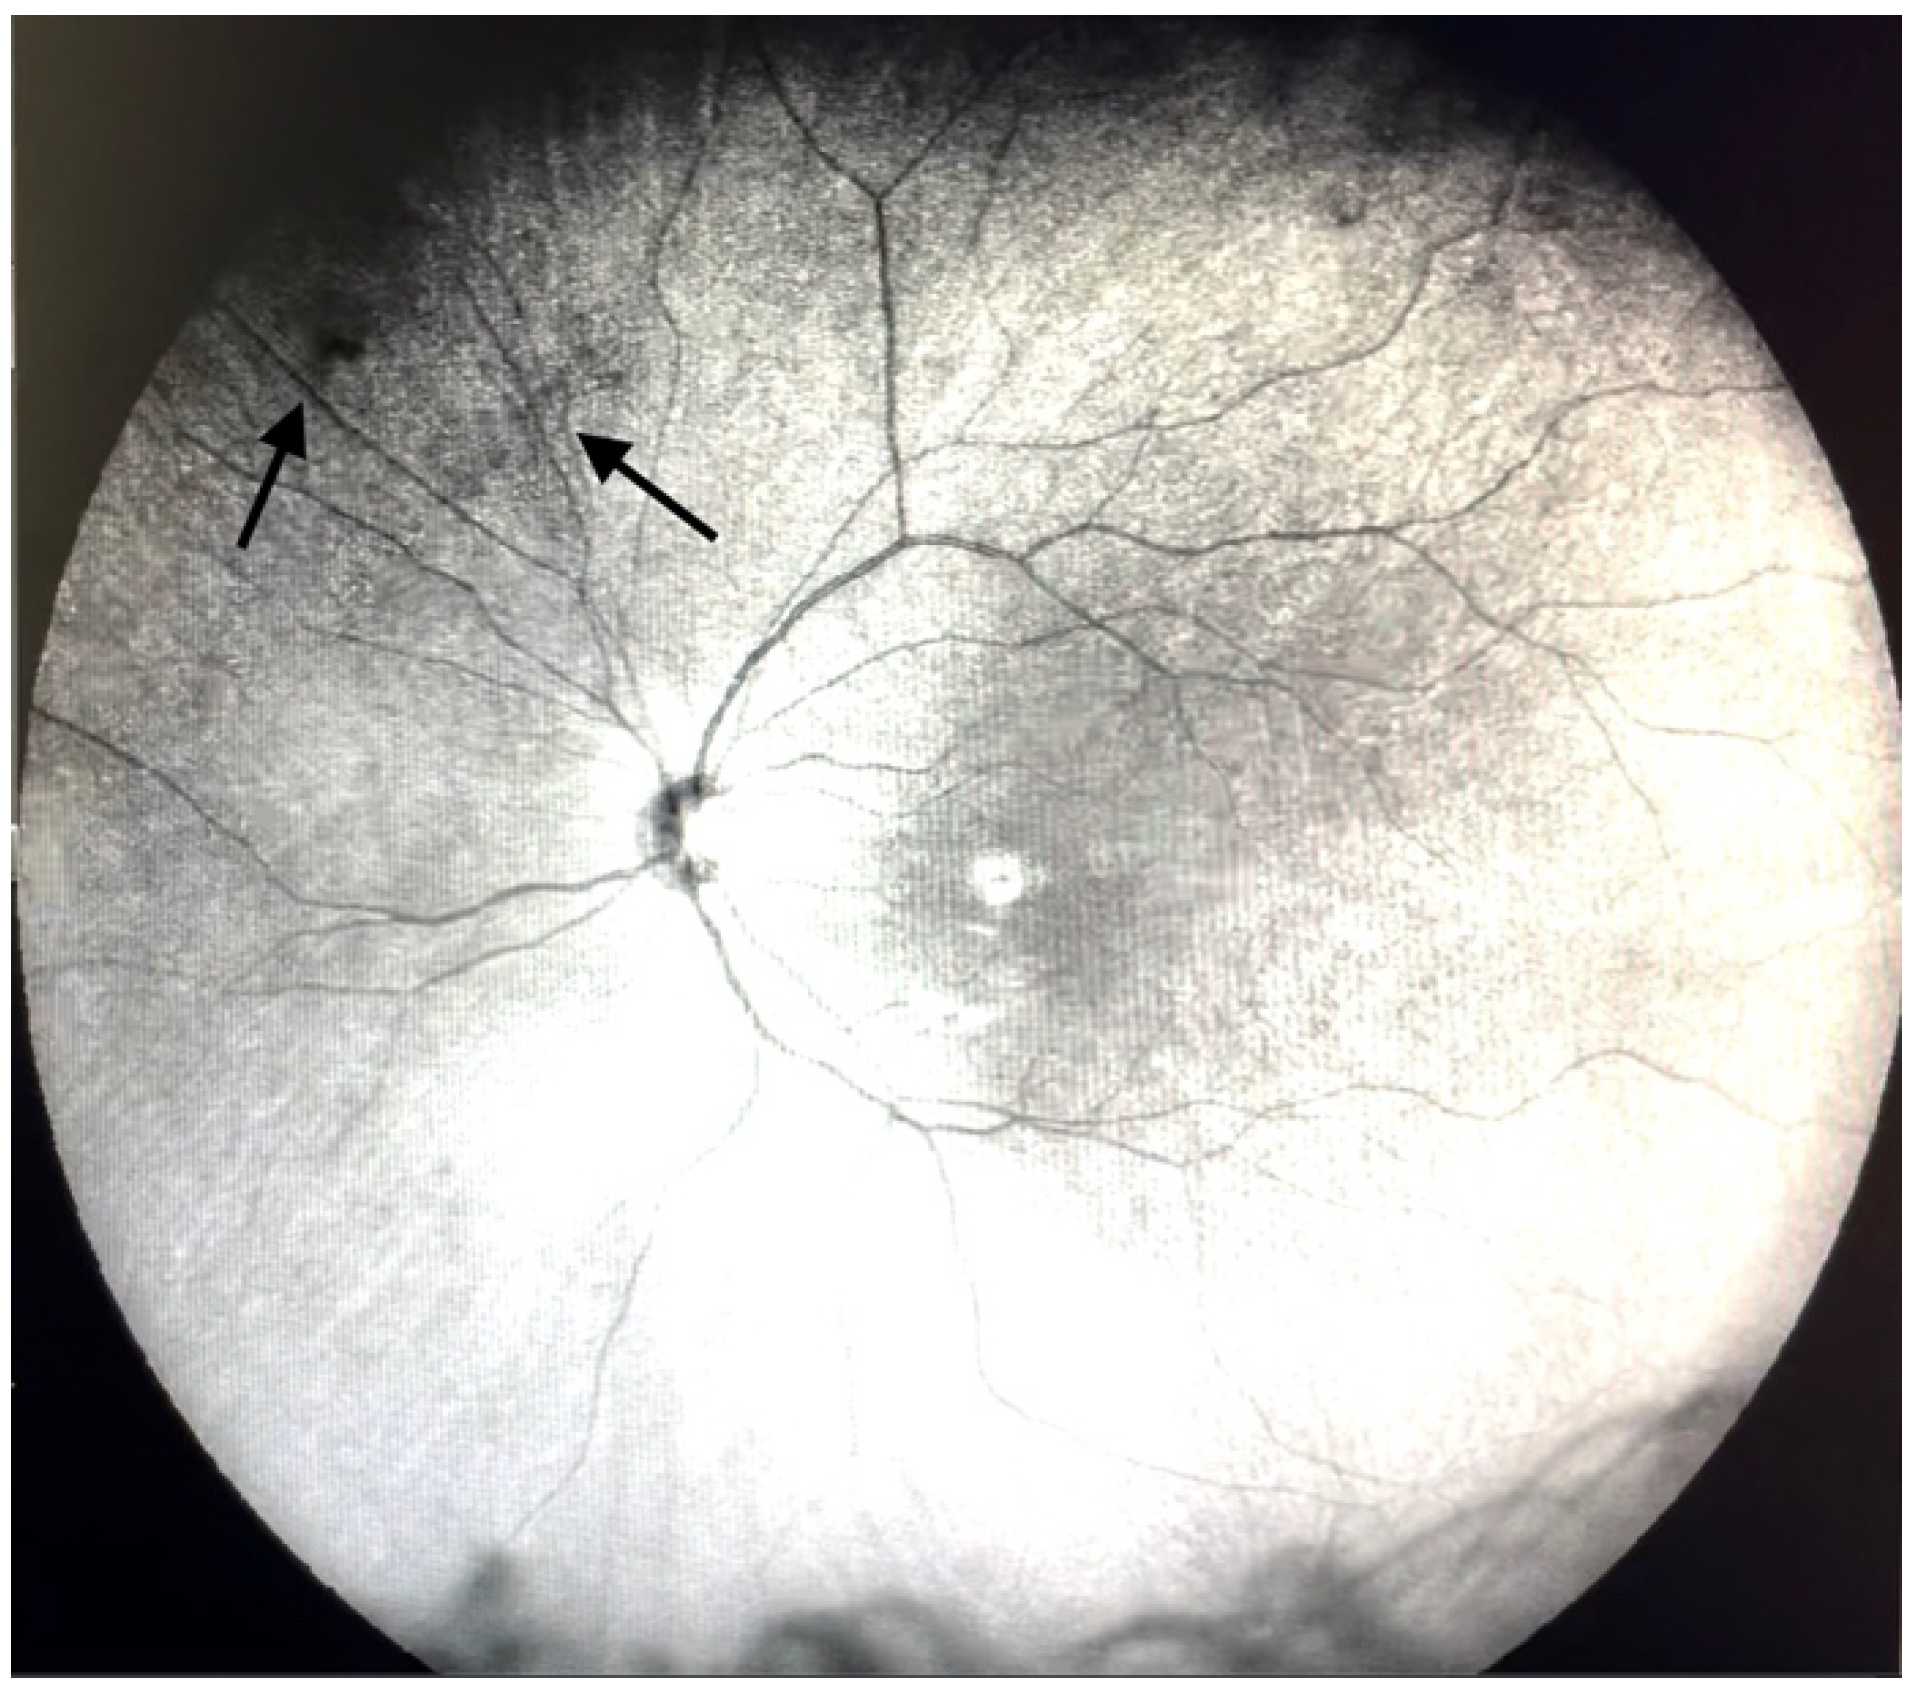

Figure 2.

Ultra-widefield IRcSLO image of an eye with Grade 1 vitreous floaters. Some diffuse shadows are observed in the superonasal periphery (arrows). See also Video S2.